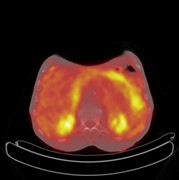

Fatal broncho-pulmonary artery fistula after lobectomy for lung cancer

Jiro Abe and others

Journal of Surgical Case Reports, Volume 2015, Issue 9, September 2015, rjv110, https://doi.org/10.1093/jscr/rjv110